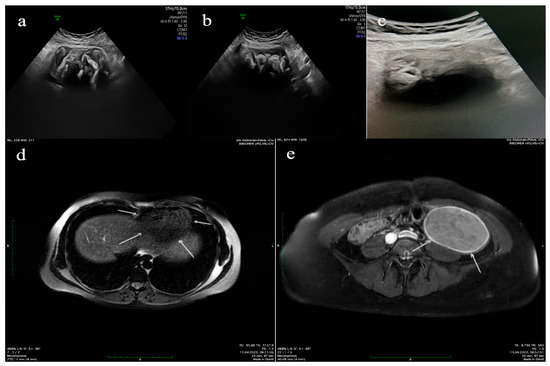

- Left adnexal tumor mass measuring 9.5 × 9.5 × 6.5 cm3; when sectioning, textile material with dimensions of 9 × 8 × 5 cm3 is evacuated; after the extraction of the textile material, the internal surface of the pseudocyst wall is intensely congestive, with greyish-yellow deposits; and isolated intramural nodular mass with dimensions of 4.5 × 4.5 × 1 cm3 of firm elastic consistency;

- Subhepatic tumor mass with dimensions of 10 × 8 × 5.5 cm3 with a grayish-pink external surface with areas of fatty tissue; when sectioning, textile material with dimensions of 7 × 6 × 4 cm3 is extracted.